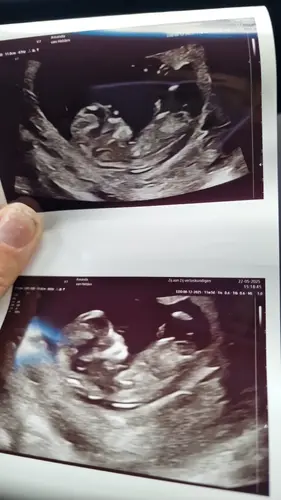

Krijg je dan ook geen afdrukken mee??? Ik heb bij alle 13 weken echo's gewoon afdrukken mee gekregen (allemaal via ziekenhuis trouwens.) ik heb a.s maandag mijn 13 weken echo staan.

Ja ik krijg alle echo's via mijn ziekenhuis omdat ik bij de gynaecoloog loop. Vorige keer 2 echo foto's meegekregen en was echt ff snel snel kijken...